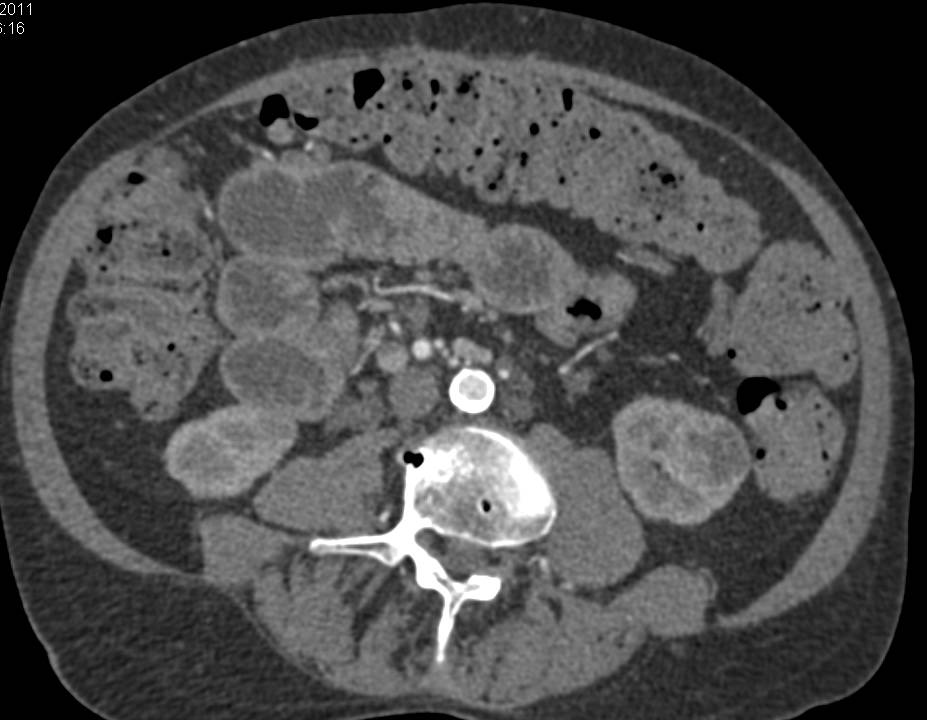

Metastatic Renal Cell Carcinoma to the Lungs